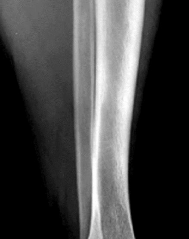

A 53-year-old man sustains a fall while skiing. He experiences immediate pain and deformity in his lower leg just above his ski boot top. Radiographs of his left lower leg are shown in Figures 1 and

After discussing operative management with the patient, you choose to proceed with an intramedullary nail. Where should blocking screws be placed to prevent the characteristic deformity of this fracture?

The patient has sustained a proximal third tibia and fibula fracture, sometimes referred to as a "boot top" fracture when sustained while alpine skiing. These fractures frequently fall into apex anterior and valgus

angulation as shown in the radiographs. Great care needs to be taken during intramedullary nailing to avoid fixing the fracture in a malreduced position. The use of Poller blocking screws in the posterior and lateral aspects of the proximal fragment can help to avoid this complication (posterior screw prevents flexion deformity while lateral screw prevents valgus deformity). Additional technical pearls include starting with a more lateral entry point for the guidewire, placing a provisional unicortical plate prior to nailing to maintain the reduction, or using a suprapatellar entry nail to allow for fixation with the knee in _a semi-extended position._